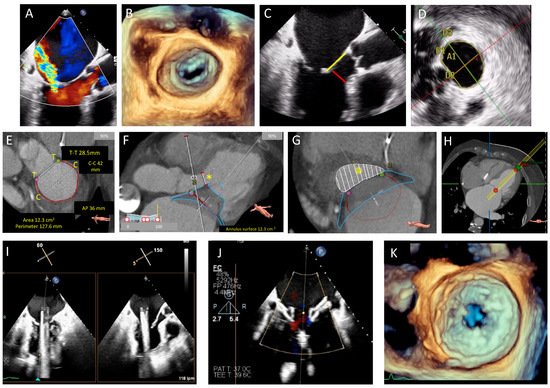

3. Echocardiography

4. Multidetector Row Computed Tomography (MDCT)